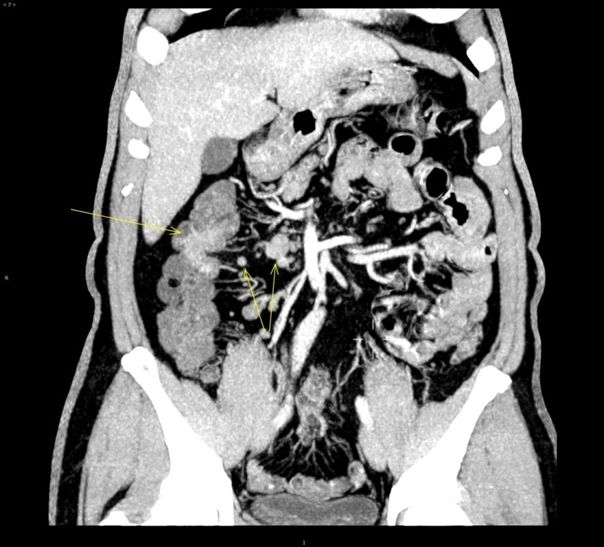

2015.1.22 肝脏MRI:肝右叶后段至尾叶肿块(大小4.9cm*5.9cm*5.4cm),肝右前叶近膈面0.9cm结节影,增强扫描边缘明显强化。

结肠癌肝转移:潜在可切;

-

治疗目的:最大程度缩小肿瘤--转化治疗--无瘤状态(NED);

治疗方案选择:全RAS基因检测;强化全身化疗:两药联合靶向。